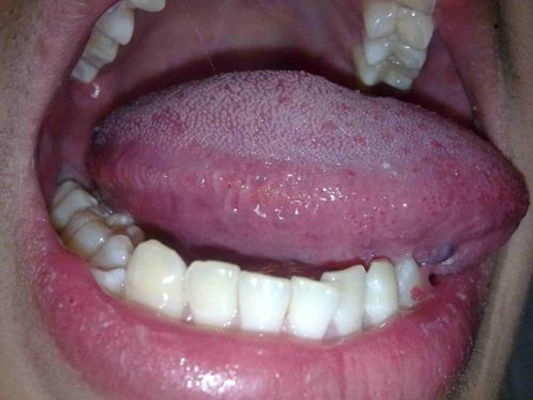

口腔念珠菌感染 (48)